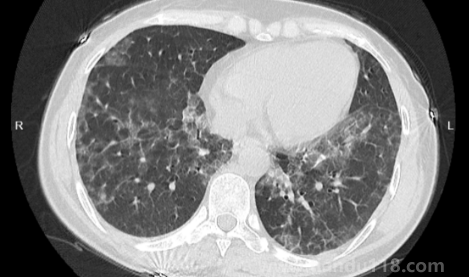

如何自查是否出現(xiàn)白肺(肺白了還能恢復(fù)嗎) 如何自查是否出現(xiàn)白肺(肺白了還能恢復(fù)嗎)白肺是目前很常見的情況,受新冠影響很多老年人都出現(xiàn)了白肺的情況,當然也有年輕人會患上白肺。那么,如何自查是否出現(xiàn)白肺?平時怎樣保護自己的肺?一起來看看天都生活網(wǎng)... 小編 2023-01-06 874 #白肺